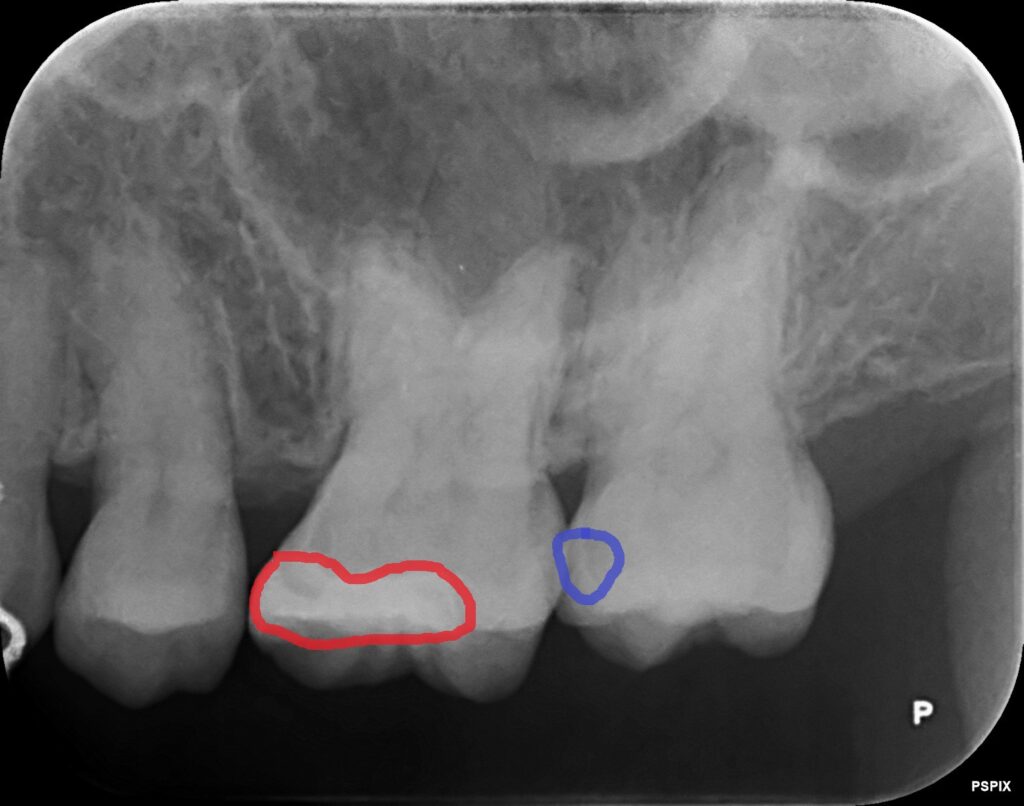

レントゲン写真を確認してみると、原因が分かりました。

赤い枠が以前治療した6番目の歯です。

もう一つ奥の7番目の歯の内部に、黒い影がありました。

青い枠で囲まれた箇所に虫歯がありました。